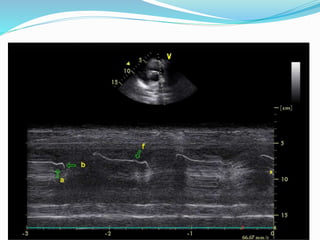

a- downward motion, concides with A-wave of MV; b- represents

onset of ventricular systole; c- max downward position ; d- closure

begins; e- closure is completed

a- downward motion,concides with A-wave of MV; b- represents onset of ventricular systole; c- max downward position ; d- closure begins; e- closure is completed